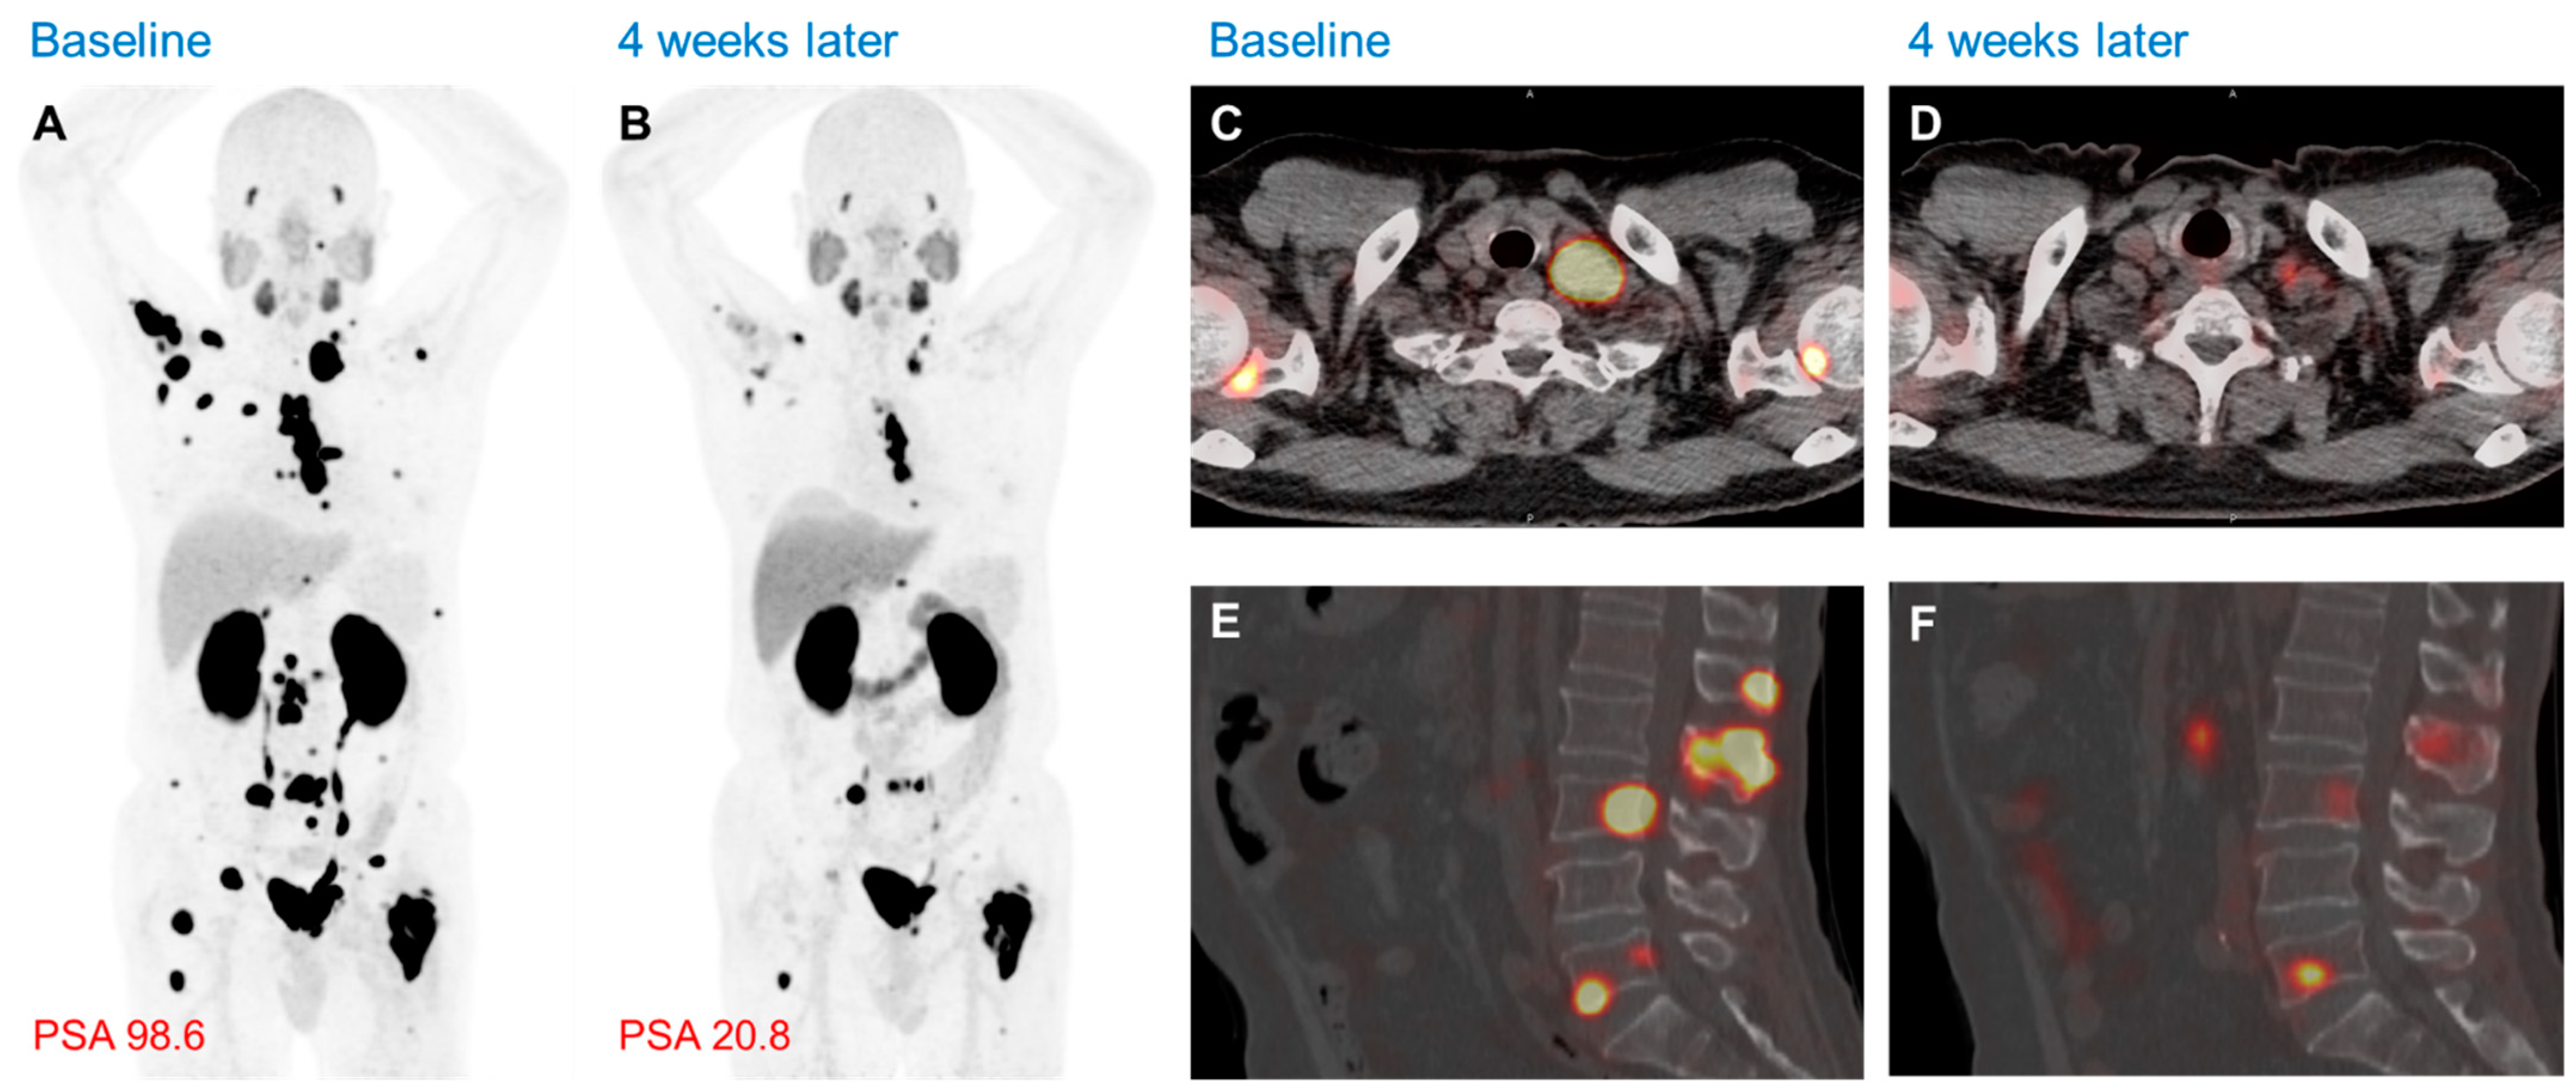

Figure 4.

Clinical response to Lu-177 Ludotadipep (FC705; second generation of PSMA inhibitor labeled with Lu-177) by F-18 PSMA PET/CT in mCRPC [71]. (A) MIP image demonstrating multifocal radioactive uptake in the metastatic lymph nodes and bones. (B) After 4 weeks of treatment with Lu-177 Ludotadipep, the MIP image revealed a decrease in radioactive uptake as well as tumor burden in the previously noted multifocal radioactive uptake lesions. The PSA level also decreased from 98.6 ng/mL to 20.8 ng/mL, which is a suitable decline according to the PSA response. (C,D) are axial fusion images to show marked regression of the left supraclavicular lymph node and bone metastases. (E,F) are sagittal fusion images to note the decreased radioactive uptake in the lumbar spine lesions.